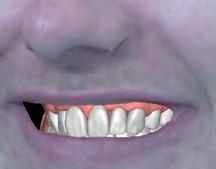

5: A treatment mock-up may be fabricated in a flexible machinable polycarbonate based on the contours of a final proposed restoration, in such a manner as to be capable of fitting to the contours of the pre-operative situation.

At the laboratory, the dental technician may merge these digitised records using Zirkonzahn.Modifier software (Zirkonzahn Srl; Gais, Italy) to form a precise 3D rendering of the patient’s pre-operative dentofacial situation, with all biomechanical and aesthetic landmarks conveniently available for reference. This offers the technician unparalleled, high-fidelity access to key diagnostic clinical information when compared to conventional analogue-based workflows.4 At this stage, an end goal of prosthodontic treatment may be developed wherein the contours of the proposed restorations are informed on the basis of the patient’s physiognomy, or rather, their unique and characteristic facial features (Figure 4).9 The final proposed design may be fabricated into a snap-on smile try-in, or treatment mock-up, using a flexible machinable polycarbonate (Temp Premium Flexible; Zirkonzahn Srl, Gais, Italy) (Figure 5).

Visualise before you provisionalise

At this early stage of diagnostic work-up, prior to any operative intervention, the clinician and the technician can now communicate to each other and, most importantly, to the patient, in an understandable visual rhetoric, a precise end goal of treatment from which a meeting of the minds may be achieved (Figures 6 and 7).5